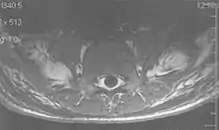

Metal artifacts

Metal artifacts occur at interfaces of tissues with different magnetic susceptibilities, which cause local magnetic fields to distort the external magnetic field. This distortion changes the precession frequency in the tissue leading to spatial mismapping of information. The degree of distortion depends on the type of metal (stainless steel having a greater distorting effect than titanium alloy), the type of interface (most striking effect at soft tissue-metal interfaces), pulse sequence and imaging parameters. Metal artifacts are caused by external ferromagnetics such as cobalt containing make-up, internal ferromagnetics such as surgical clips, spinal hardware and other orthopaedic devices, and in some cases, metallic objects swallowed by people with pica.[3] Manifestation of these artifacts is variable, including total signal loss, peripheral high signal and image distortion (Figs 3 and 4).[1] Reduction of these artifacts can be attempted by orientating the long axis of an implant or device parallel to the long axis of the external magnetic field, possible with mobile extremity imaging and an open magnet. Further methods used are choosing the appropriate frequency encoding direction, since metal artifacts are most pronounced in this direction, using smaller voxel sizes, fast imaging sequences, increased readout bandwidth and avoiding gradient-echo imaging when metal is present. A technique called MARS (metal artifact reduction sequence) applies an additional gradient, along the slice select gradient at the time the frequency encoding gradient is applied. ==Signal processing dependent artifacts== The ways in which the data are sampled, processed and mapped out on the image matrix manifest these artifacts.[1]